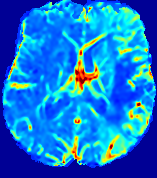

LesionRefer to captionRefer to captionRefer to captionRefer to captionRefer to captionRefer to caption𝐕rgbsubscript𝐕𝑟𝑔𝑏{\bf{V}}_{rgb}Refer to captionRefer to captionRefer to captionRefer to captionRefer to captionRefer to caption𝐕2subscriptnorm𝐕2{\|\bf{V}}\|_{2}Refer to captionRefer to captionRefer to captionRefer to captionRefer to captionRefer to captionRefer to caption3.53.53.52.82.82.82.12.12.11.41.41.40.70.70.70.00.00.0(mm/s)𝑚𝑚𝑠(mm/s)D𝐷DRefer to captionRefer to captionRefer to captionRefer to captionRefer to captionRefer to captionRefer to caption0.0200.0200.0200.0160.0160.0160.0120.0120.0120.0080.0080.0080.0040.0040.0040.0000.0000.000(mm2/s)𝑚superscript𝑚2𝑠(mm^{2}/s)Slice #1Slice #2Slice #3Slice #4Slice #5Slice #6

Figure 4: PIANO feature maps for another patient in the ISLES 2017 training set, where the lesion is located in the right hemisphere. Top row: segmented stroke lesion region (white) on different slices. The corresponding slices for the PIANO feature maps are shown in the following rows.

For a better insight into an estimated velocity field 𝐕𝐕{\bf{V}} and diffusion field 𝐃𝐃{\bf{D}}, we compute the following maps: (1) 𝐕rgbsubscript𝐕𝑟𝑔𝑏{\bf{V}}_{rgb}: Color-coded orientation map of 𝐕=(Vx,Vy,Vz)T𝐕superscriptsuperscript𝑉𝑥superscript𝑉𝑦superscript𝑉𝑧𝑇{\bf{V}}=(V^{x},V^{y},V^{z})^{T}, obtained by normalizing 𝐕𝐕{\bf{V}} to unit length and mapping its 3 components to red, green, blue respectively; (2) 𝐕2subscriptnorm𝐕2\|{\bf{V}}\|_{2}: 222 norm of 𝐕𝐕{\bf{V}}; (3) D𝐷D: scalar field in Eq. 5.

Fig. 3 and Fig. 4 show the PIANO feature maps estimated from two ISLES 2017 patients: all are highly consistent with the lesion in both cases. Details of the blood flow trajectories are revealed in 𝐕rgbsubscript𝐕𝑟𝑔𝑏{\bf{V}}_{rgb} by the ridged patterns and the sharp changes of colors in the unaffected (right) hemisphere, while the flat patterns appearing within the lesion provide little directional information about the velocity and indicate low velocity magnitudes. Velocity magnitudes are more directly visualized via 𝐕2subscriptnorm𝐕2\|{\bf{V}}\|_{2}, from which one can easily locate the lesion where 𝐕2subscriptnorm𝐕2\|{\bf{V}}\|_{2} is low. D𝐷D also indicates lower diffusion values in the lesion, though with less contrast potentially due to the fact that it captures the accumulated effect of CA diffusion at the voxel-level.